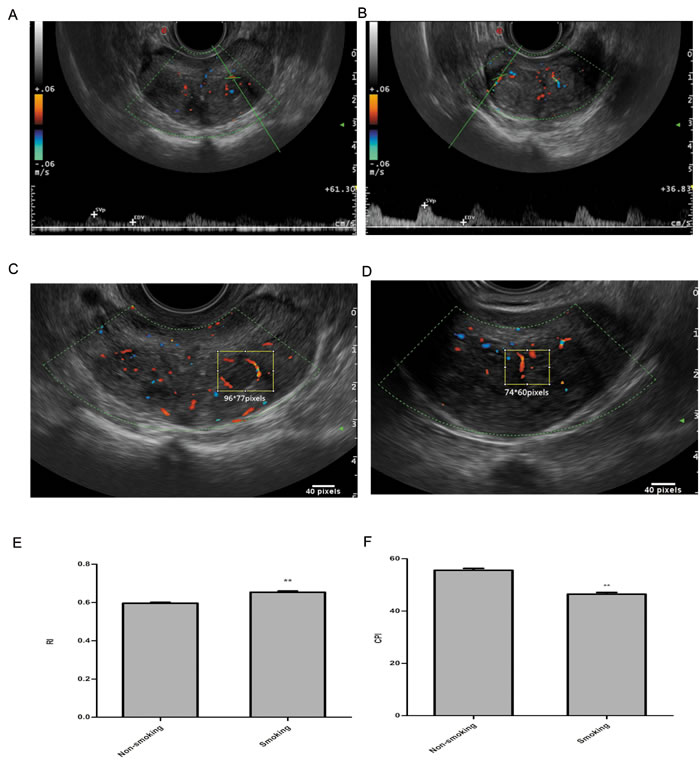

Data were obtained from 268 patients who underwent HoLEP during a 1-year period. The baseline characteristics of patients are listed in Table 1. A slightly decreased prostate volume was observed in smoking patients (P = 0.04). The blood metabolic tests revealed that testosterone was significantly elevated in the smoking group (P < 0.01), whereas there were no significant differences in the other aspects, including serum PSA levels. CDUS data were collected preoperatively and divided into non-smoking vs. smoking groups according to the criteria. Interestingly, the vessel RI was significantly enhanced in the smoking group compared with the non-smoking group (P < 0.01). The results of the CPI are shown in Figure 1. It was significantly decreased in smoking patients (P < 0.01).

Figure 1: Representative images and analysis of RI and CPI in transrectal colour Doppler ultrasound on prostatic blood flow. A. RI for TZ vascular bundles of non-smokers, B. RI for TZ vascular bundles of smokers, C. CPI measurements of non-smokers, D. CPI measurements of smokers E. TZ vascular RI comparison between smokers and non-smokers; F. vascular CPI comparison between smokers and non-smokers; P* < 0.05, P** < 0.01.

BPH, which is caused by an increased number of cells in the prostatic TZ, is also characterized by a change in vascularization. As a previous study reported, vascular damage and prostate cell proliferation share a common pathogenic mechanism. The vessel RI is low in healthy patients and is advanced in BPH patients. Some studies have attributed this finding to compressed arteries between the peripheral zone (PZ) and the TZ, resulting in a marked increase in the RI of the capsular arteries[37]. Other studies investigating the vascular anatomy of the normal prostate have found notable differences between the RI values of the PZ and TZ. These studies have reported significantly higher RI and lower CPI induced by diabetes in TZ but not in PZ [3]. In this study, we only analysed the CPI and RI in the TZ. We found that RI was significantly elevated smoking group compared with non-smokers (0.59 ± 0.05 vs. 0.65 ± 0.06, P < 0.01). Furthermore, decreased prostate volume was observed in the smokers after excluding the elevated compression from the enlarged PZ. These findings indicated significant vascular damage with increased vascular resistance in the smoking patients. CPI, as an analysis of tissue perfusion, confirmed the results that vessel damage resulted in poor organ perfusion of the prostate. Although CD34 showed the presence of increased microvessels in the prostates of smokers, organ hypoperfusion may still exist.